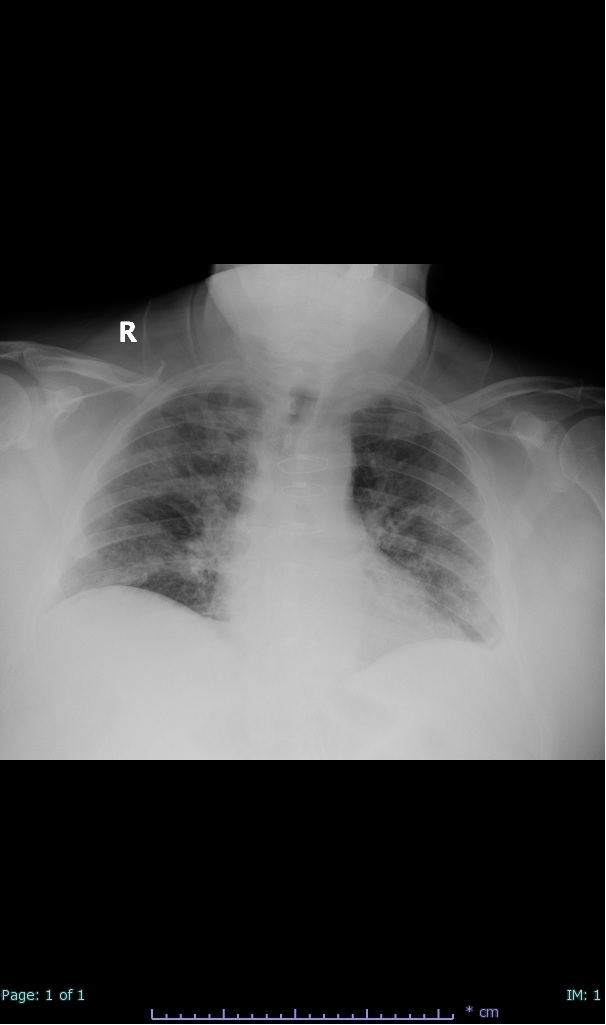

- 100% subpleural involvement, 33% + centrolobular involvement

- 40% even apical/basilar, 27% basilar dom, 5% mid dom. 1/17

- 66% had some + CXR finding I could correlate to a CT finding